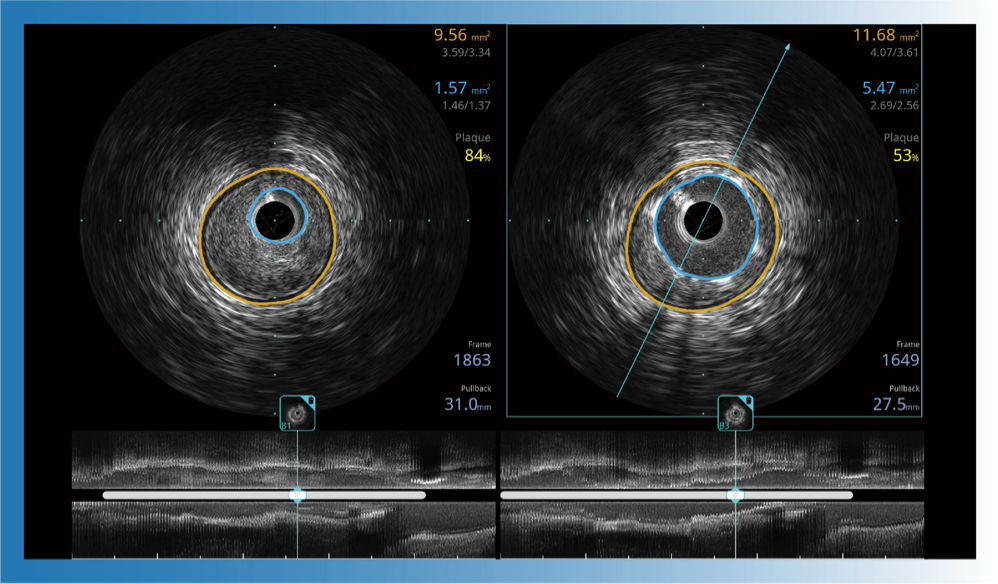

治疗前后两次测量录像对比

简化疗效评估

一键智能描迹,自动测量斑块负荷、面积狭窄率等指标,准确率高于90%